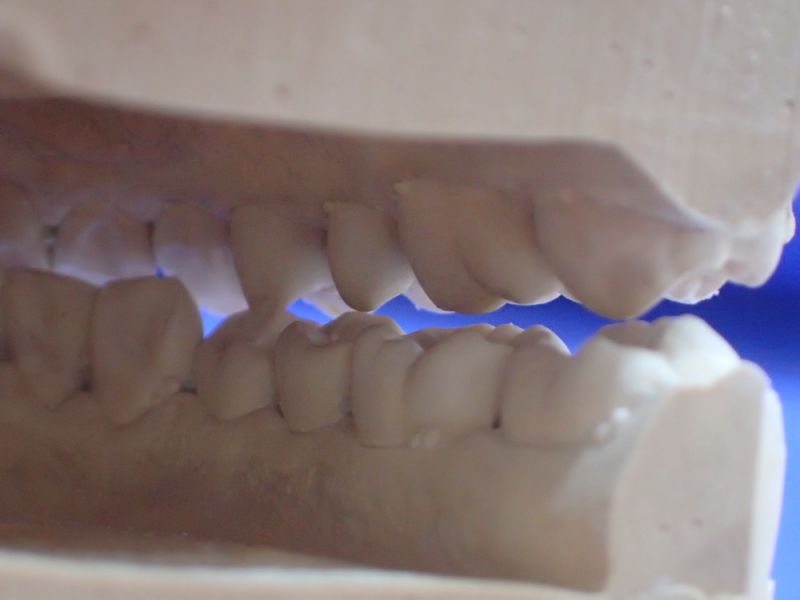

Daraufhin hat der Patient eine Kieferorthopädin konsultiert, die sich nach eigener Einschäötzung auf das Thema CMD spezialisiert hat. Ohne Vordiagnostik hat daraufhin eine Kieferorthopädische Erwachsenenbehandlung begonnen, die mit einer Bebänderung des Oberkiefers begann und nach kurzer Zeit zu geradezu explosionsartig verstärkten Bescherden des Patienten führte. Darauf angesprochen erklärte die konsultierte Kieferorthopädin, nach inzwischen 6000,-€ Behandlungskosten sie wisse nicht mehr weiter und könne dem Patienten nicht helfen.

Es erfolgt dieErstuntersuchung und die Herstellung und Eingliederung eines adjustierten Aufbissbehelfs zum Nachweis einer CMD.